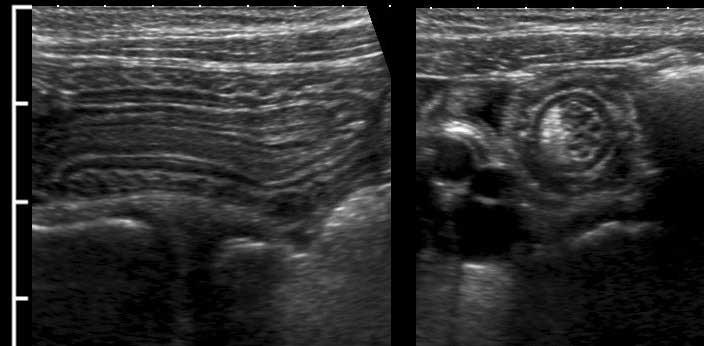

So sánh hồi tràng bình thường (trái) và hồi tràng trong bệnh Crohn (phải), không nén (hình trên) và có nén (hình dưới).

Note the same cm-scale in all four US-images.

Độ dày thành đơn ở người bình thường là 1,5 mm, ở bệnh nhân Crohn là 6,5 mm